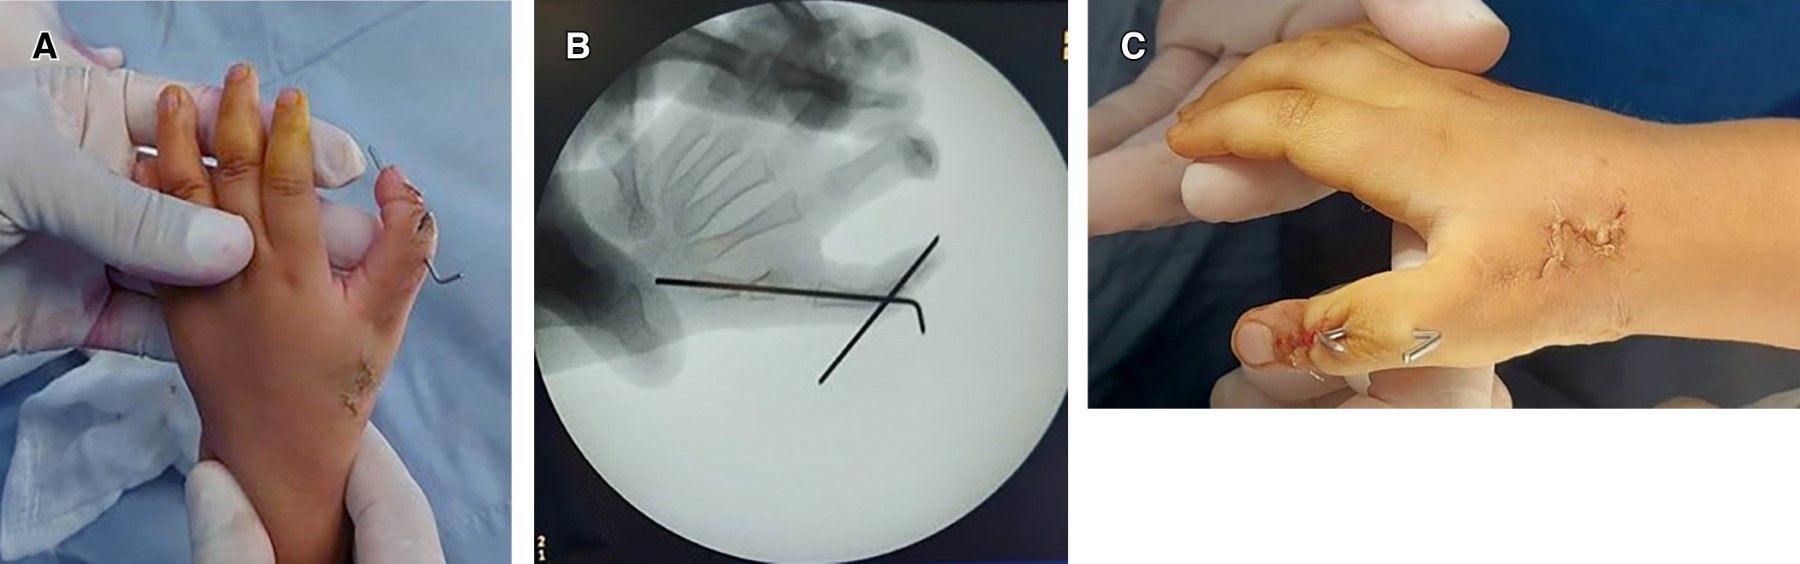

Se procede a realizar una segunda intervención quirúrgica, se inicia por mano derecha, bajo anestesia general con la paciente en decúbito supino, con isquemia mediante vendaje smarch y bajo visión microquirúrgica, se procede a con osteotomía de reducción, rotación y abducción de primer metacarpiano, se realiza una incisión en Z en cara dorsal de primer metacarpiano y disección por planos, se realiza una ventana entre extensor policis brevis y extensor policis longus, posteriormente procedemos a realizar una diafisectomía oblicua a nivel de diáfisis media de primer metacarpiano, realizando un acortamiento de 1 cm de la longitud de metacarpiano, así como restauración en la abducción y rotación interna de todo el pulgar, se procede a mantener la posición mediante un clavillo Kirschner de 1.2 mm, posteriormente se procede a realizar una incisión en H a nivel de segundo y tercer metacarpiano, procedemos a realizar disección por planos, ubicamos la articulación interfalángica distal y procedemos a realizar resección de cápsula articular en su totalidad, posteriormente procedemos a ubicar la porción fisaria de la tercer falange, y realizamos una resección de la porción epifisaria, procedemos a realizar remodelación de segmento distal conservando la inserción del extensor policis longus, posteriormente procedemos a realizar una osteotomía en tercio proximal de segunda falange, transversa , con un margen de 0.7 mm de distancia de la zona fisaria sin lesionarla, seguida de una fijación entre el segmento distal de la tercera falange y el segmento proximal de segunda falange fijándola mediante un clavillo Kirschner de 1.2 mm, se procede a con irrigación de heridas se corrobora adecuada fijación mediante fluoroscopia, se realiza sutura de con monocryl 3-0, se retira isquemia corroborando ausencia de sangrado activo, se procede a colocar una férula tipo corbata y un vendaje simple, posteriormente se realiza mismo procedimiento quirúrgico en mano izquierda, con una duración total de 2 horas y 30 minutos, con un sangrado mínimo, tiempo de isquemia por miembro superior de 1 hora y 10 minutos, sin complicaciones transoperatorias (Figura 5).

La paciente egresa a su domicilio, con profilaxis antibiótica a base de cefalotina y analgésicos, se mantiene vigilancia estrecha semanal en la consulta externa para valoración de heridas y llenado capilar. Se realiza valoración a las cinco semanas postquirúrgicas con nueva radiografía de control, donde se observa adecuada cicatrización de tejidos blandos, sitio de entrada de calvillos sin datos de sangrado o exudado, sin presencia de eritema (Figura 6); acude con radiografía de control donde se observan datos de consolidación ósea a nivel de primer metacarpiano, así como una fusión entre la porción proximal de f2 y la porción distal de f3 de ambos pulgares (Figura 7), clínicamente sin dolor, se retiran clavillos y se envía a rehabilitación. Un año posterior al segundo evento quirúrgico la paciente es valorada, encontrando mano derecha e izquierda con presencia de pulgar con adecuado aspecto (dos falanges, un pliegue de flexión interfalángico bien definido, lamina ungueal con crecimiento uniforme y altura del pulgar con relación a los demás dedos), en ligera rotación interna, con arcos de movilidad con adecuada abducción, extensión, flexión y oposición, presencia de pinza fina y gruesa, con adecuada fuerza muscular, sensibilidad conservada de forma bilateral (Figura 8).